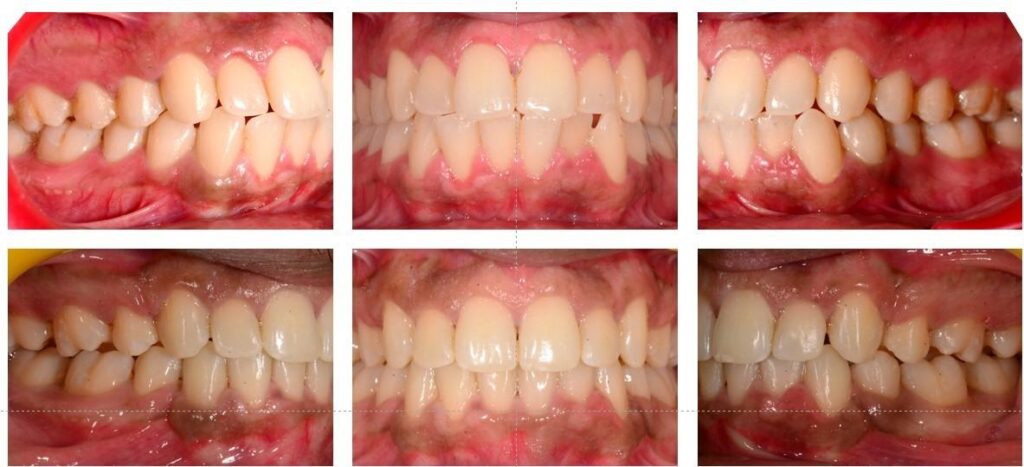

Treatment Results-Before & After

Mar’22 to Dec’24(Timeline)

Dental Improvements

- Full resolution of crowding

- Proper space closure with good root control

- Improved overjet and overbite

- Stable Class I occlusion

Facial Aesthetics

- Noticeable reduction in upper and lower lip protrusion

- Soft-tissue profile became more balanced

- Patient reported improved confidence in side-profile photographs

After premolar extraction with Invisalign, the face often looks more balanced. If your teeth were pushed forward before, retraction allows the lips to settle naturally. This creates a softer and more refined facial outline.